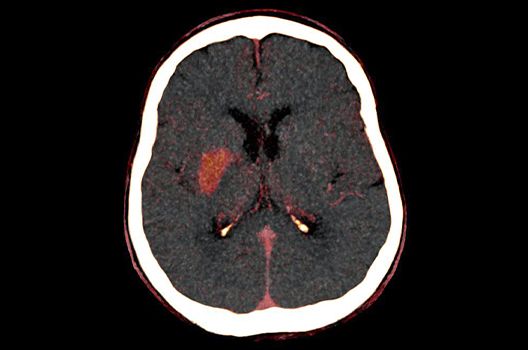

Die Hybridbildgebung mittels PET/MRT spielt insbesondere in der onkologischen Bildgebung eine wichtige Rolle. Eine mögliche Fragestellung ist die Unterscheidung zwischen einem Tumorrezidiv oder therapeutisch assoziierten Veränderungen insbesondere dann, wenn diese Frage mittels MRT alleine nicht beantwortet werden kann.

Die bildgebende Diagnostik und Verlaufsbeurteilung von Tumoren des Nervensystems ist einer der klinischen und Forschungsschwerpunkte unserer Abteilung. Eine besondere Bedeutung kommt der Hybrid-Bildgebung zu. Das Universitätsklinikum verfügt über einen integrierten Ganzkörper-PET/MRT-Scanner, der die Vorteile der MRT-Bildgebung und der Positronenemissionstherapie (PET) vereinigt. Aufgrund der langjährigen klinischen Arbeit und Forschungstätigkeit mit diesem Gerät hat die Neuroradiologie Tübingen maßgeblich zur Etablierung dieses Verfahrens beigetragen. Auch weiterhin forschen wir intensiv an neuen Methoden zur frühen Einordnung von Tumoren und insbesondere Tumorrezidiven, die mit anderen Methoden häufig nicht erfasst werden können.